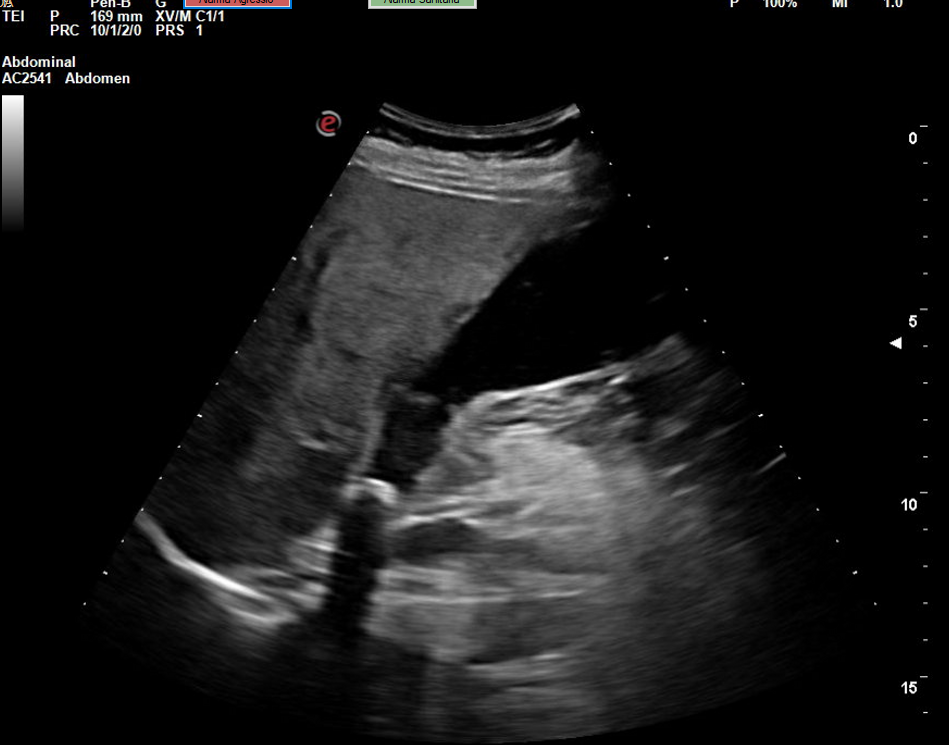

Descripción de los hallazgos ecográficos y las imágenes más relevantes para la resolución del caso

Se realiza la ecografía abdominal en el ambulatorio, donde se objetiva colelitiasis con el colédoco en el límite superior de la normalidad (4,4 mm), también presenta esteatosis hepática grado I. El resto de la ecografía no presenta hallazgos de interés.